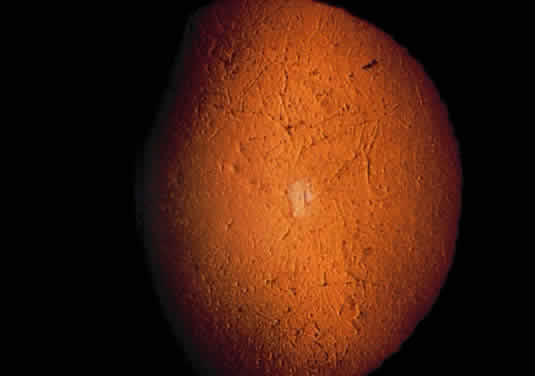

Tissue pigmentation (ochronosis) is not caused by the presence of homogentisic acid, which is bound physically to the connective tissue macromolecules, but rather by the chemical binding in the tissues of alternative pathway by-products resulting from the failure to remove homogentisic acid in a normal manner. These by-products are benzoquinoacetic acid and polymers of this compound. The production of both benzoquinoacetic acid and its polymers depends on the presence of the homogentisic acid polyphenol oxidase, which is present in the skin and cartilage of mammals. Once deposited, these polymers are indistinguishable from melanin (Fig. 2).3

OCULAR FINDINGS. The outstanding clinical feature common to all three phenotypes is the corneal and conjunctival cystine crystal deposition (Figs. 3 and 4). Photophobia is often the only presenting visual symptom; this may be incapacitating and associated with blepharospasm.

The retinal abnormality consists of a generalized depigmentation that may assume a patchy pattern. At first the pigmentary disturbance tends to be peripheral, but it progresses with age. Macular abnormalities have been observed.39 Intracellular crystals also have been seen in the retinal pigment epithelial cells during electron microscopy.